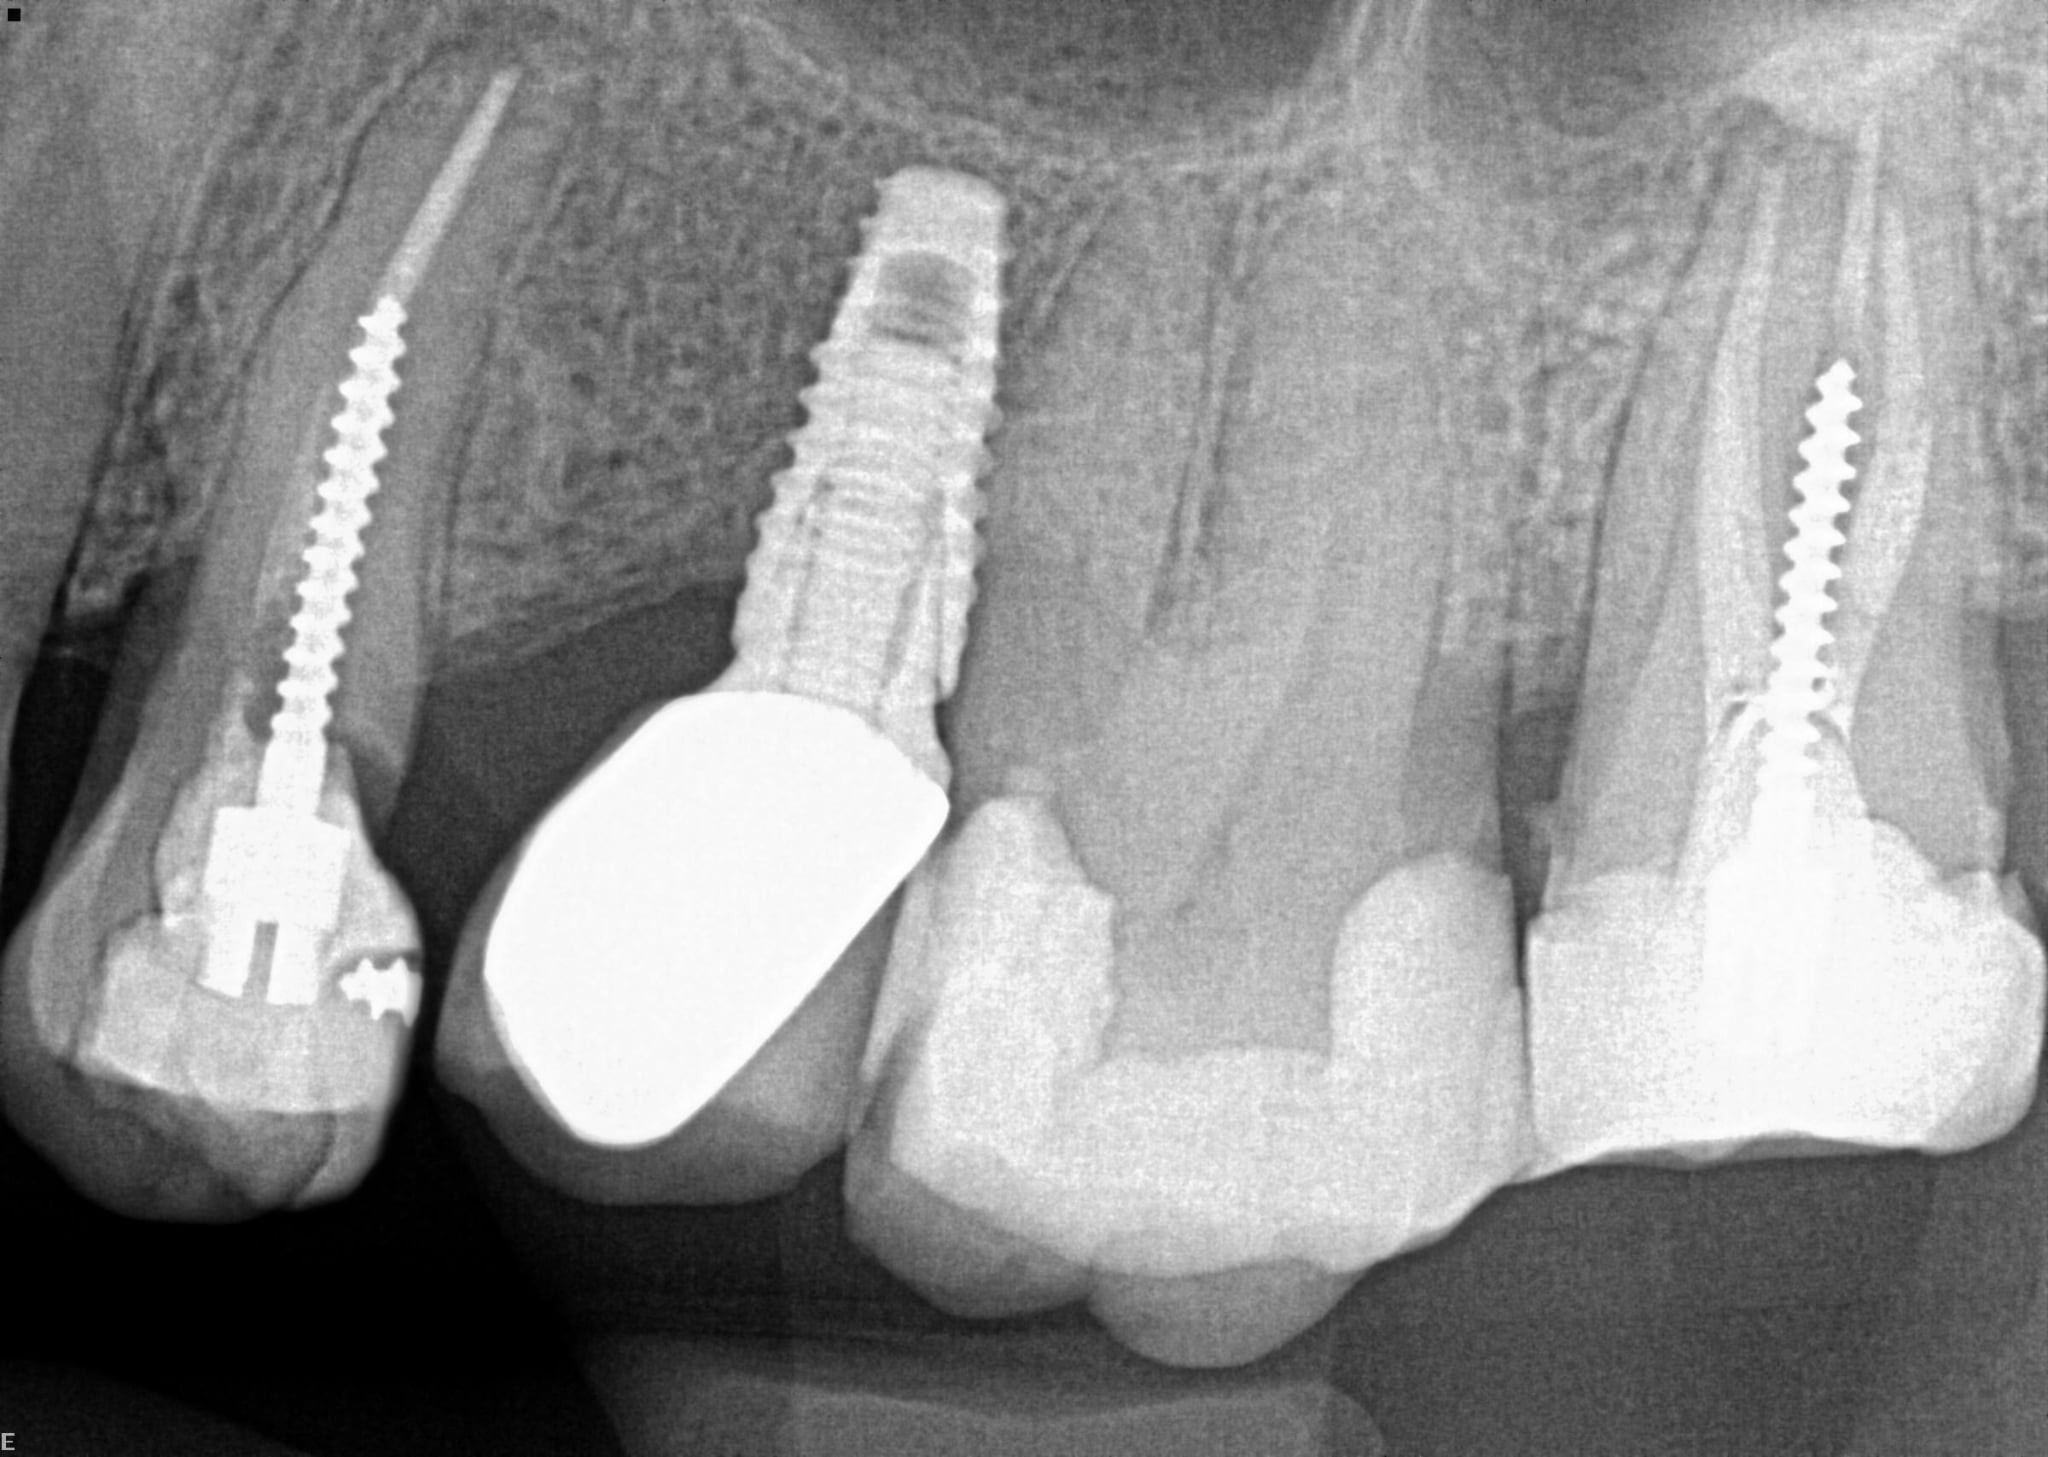

2. What option can describe the post placement in the X ray bellow for the tooth # 4.6?